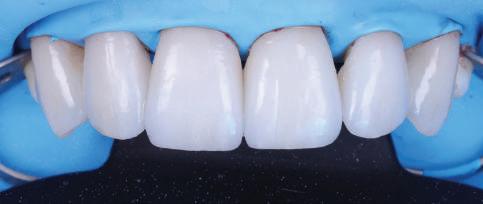

КРАТКО ОПИСАНИЕ

КЛИНИЧНИЯ СЛУЧАЙ

Пациентът постъпи в клиниката с молба за тотална рехабилитация на усмивката. Той не харесваше централ ните си резци, които според него бяха твърде къси и квадратни. Имаше раз стояние от медиално и дистално на латералните му резци. Друго сериоз но оплакване бе свързано с металоке рамичната корона на зъб 12, която бе жълтеникава и неестетична, като цяло не харесваше вида на венците си и както самият той се изразяваше, „вижда се прекалено много от венците при усмивка“.

ЛЕЧЕБНИЯТ ПЛАН ПРИ ТОЗИ СЛУЧАЙ БЕШЕ СЛЕДНИЯТ: Диагностика, фотодокументация,

циментиране на фасетата върху него).

След диагностиката бяха направени екстра- и интраорални снимки, както и рентгенографии; професионалното почистване бе от изключителна важ ност, бяха дадени и инструкции за лич на орална хигиена. Бе направено интра орално сканиране с Medit i500. Цялата тази информация бе използ вана в приложението Smilecloud за 2D биометричен дизайн. В приложението са налични естест вени форми на зъбите и щом бяха под брани зъби и бе направен дизайн

библиотеката на Exocad. Струва си да се отбележи, че 2D дизайнът от Smile Cloud бе спазен до последния детайл в Exocad smile creator с цел да се създаде 3D obj файл със зъбните форми. След като естетичният дизайн бе готов в model creator модула на Exocad, адитивен 3D мок-ъп модел бе експорти ран и принтиран от принтер Formlabs 3. Моделът бе използван за направата на силиконов водач, за да се изготви мо тивационен мок-ъп в устата на паци ента и да се оценят естетичните па раметри. След като пациентът одобри вида на усмивката си, мок-ъпът бе използван за финализиране дизайна на усмивка та. Мок-ъпът бе използван също така като водач по време на мекотъканна та хирургия, както и при препарация на зъбите.

Препарираните зъби бяха импорти рани в Exocad и насложени върху ес тествените форми от биометричния дизайн, като така стана ясно дали зъ бите са били препарирани коректно. По този начин зъболекарят и зъботехни кът работят в една и съща екосистема и резултатът е оптимален. С короната се справихме чрез диги тална редукция на циркония в Exocad, като по този начин на практика създа дохме циркониево кепе, след което про изведохме фасета от IPS Empress Cad Multi. Кепето от Katana Zirconia на зъб 12 с букално послойно нанесена керами ка бе фрезовано (послойното нанасяне бе направено, за да се подобри връзката и да се осигури адхезивно циментиране на фасетата към циркониевото кепе, както и за да се напасне цветът към този на съседните зъби). При първото сканиране регистрирах ме цялата горна зъбна дъга, така че, ко гато се наложи да сканираме повторно, бе изтрит и сканиран наново само зъб 12, тъй като венците не бяха отдръп нати при второто сканиране.

10 Dental Tribune Bulgarian Edition / октомври 2022 г.

НА

рентгенографии. Инициална терапия и професионално почистване. Интраорално сканиране с цел диги тално планиране. Регистрация и 3D ориентиране на ок лузалната равнина на горна и долна челюст в пространството. 2D дигитално планиране и дизайн на усмивката посредством приложение то Smile Cloud. 3D дигитално планиране и дизайн на функционалните и естетичните па раметри. 3D дигитален дизайн и адитивен мокъп на горна челюст. 3D принтиране и мок-ъп модели. Мотивационен мок-ъп. Фини корекции за постигане на фи налния дизайн. Мекотъканна хирургия с мок-ъпа като водач Препарация през мок-ъпа, използвай ки дизайна като водач за финалната препарация в Exocad. Циркониево кепе ще бъде циментира но с цел адхезивно залепяне на фасе та на края. Кепето има същия цвят като този на съседните зъби, за да може фасетата да се впише перфект но в цялостната усмивка. Изработване на 12 IPS Empress Cad Multi фасети с послойно нанесена ке ТОТАЛНА РЕХАБИЛИТАЦИЯ НА УСМИВКАТА С ИЗЦЯЛО ДИГИТАЛЕН ПРОТОКОЛ Д-р Калин Маринов и зт. Стефан Петров рамика букално върху зъбните препа рации и върху първичното циркони ево кепе (има възможност за ецване и адхезивно

Една седмица след препарацията на зъбите и циментирането на цирко ниевото кепе бяха изработени 12 IPS Empress Cad Multi фасети. Макро- и микротекстурата на фасе тите бяха направени на ръка, след кое то бяха нанесени 3D характеризации с боички, а полирането отново бе напра вено ръчно, за да им се придаде естест вен и естетичен вид. Предизвикателството тук беше короната да има същите оптични характеристики като тези на остана лите зъби при естествена светлина, през поляризационен и флуоресцентен филтър. 3D принтерът бе Fromlabs, софтуерът за фрезоване – Mill Box, а фрез апаратът –imes icore CORiTEC 350i. В крайна сметка постигнахме ес тествен вид на усмивката с натурал на зъбна морфология при изцяло диги тален протокол, при който дизайнът бе направен първоначално и през всич ки етапи на лечението се придържахме към него до самия край Излишно е да отбелязваме, че всички сме удовлетворени от постигнатото! Преди След Победител в категория „Клиничен случай с изцяло дигитален протокол“ в конкурса „Усмивка на годината 2022“

11Dental Tribune Bulgarian Edition / октомври 2022 г. Преди лечението Фиг. 1 Фиг. 2 Фиг. 3 Фиг. 4 Фиг. 5 Фиг. 6 Фиг. 7 Фиг. 9 Фиг. 10 Фиг. 11 Фиг. 8 Фиг. 12 Фиг. 13

12 Dental Tribune Bulgarian Edition / октомври 2022 г. По време на лечението Фиг. 14 Фиг. 16 Фиг. 20 Фиг. 23 Фиг. 21 Фиг. 24 Фиг. 26 Фиг. 28 Фиг. 31 Фиг. 34 Фиг. 29 Фиг. 32 Фиг. 35 Фиг. 30 Фиг. 33 Фиг. 36 Фиг. 27 Фиг. 22 Фиг. 25 Фиг. 17 Фиг. 18 Фиг. 19 Фиг. 15

13Dental Tribune Bulgarian Edition / октомври 2022 г. След лечението За авторите: Д-р Калин Маринов е специалист в областта на имплантологията, протетиката и естетичната хирургия. Завършил е дентална медици на в София през 2012 г. През 2014 г. основава Sky Dental Clinic. Бил е на обмен ни начала в катедра „Протетика“ на Университета по дентална медицина във Фрайбург, Германия. Живял е и е практикувал в Мелбърн, Австралия, и е посеща вал курсове и лекции в Италия, Швейцария, Германия с насоченост в естетич ната хирургия и имплантология, както и тоталната рехабилитация на устна та кухина чрез импланти. Зт. Стефан Петров основава собствена лаборатория през 2006 г. Официален демонстратор на GC за България, като от 2015 г. е KOL за Източна Европа. Инструктор е на Straumann за България. Лаборатория та му има сертификат за пилотна лаборатория на Micerium – Италия. Носител е на множество награди в денталния конкурс „Усмивка на годината”. Носител е на награда CERAMISTS MASTER CUP с д-р Софиен Риахи в престижния международен конгрес CERAMISTS – NO LIMITS 2015 г. Изнася лекции и провежда курсове в редица европейски страни. Фиг. 37 Фиг. 40 Фиг. 43 Фиг. 45 Фиг. 47 Фиг. 50 Фиг. 48 Фиг. 49 Фиг. 41 Фиг. 44 Фиг. 46 Фиг. 42 Фиг. 38 Фиг. 39